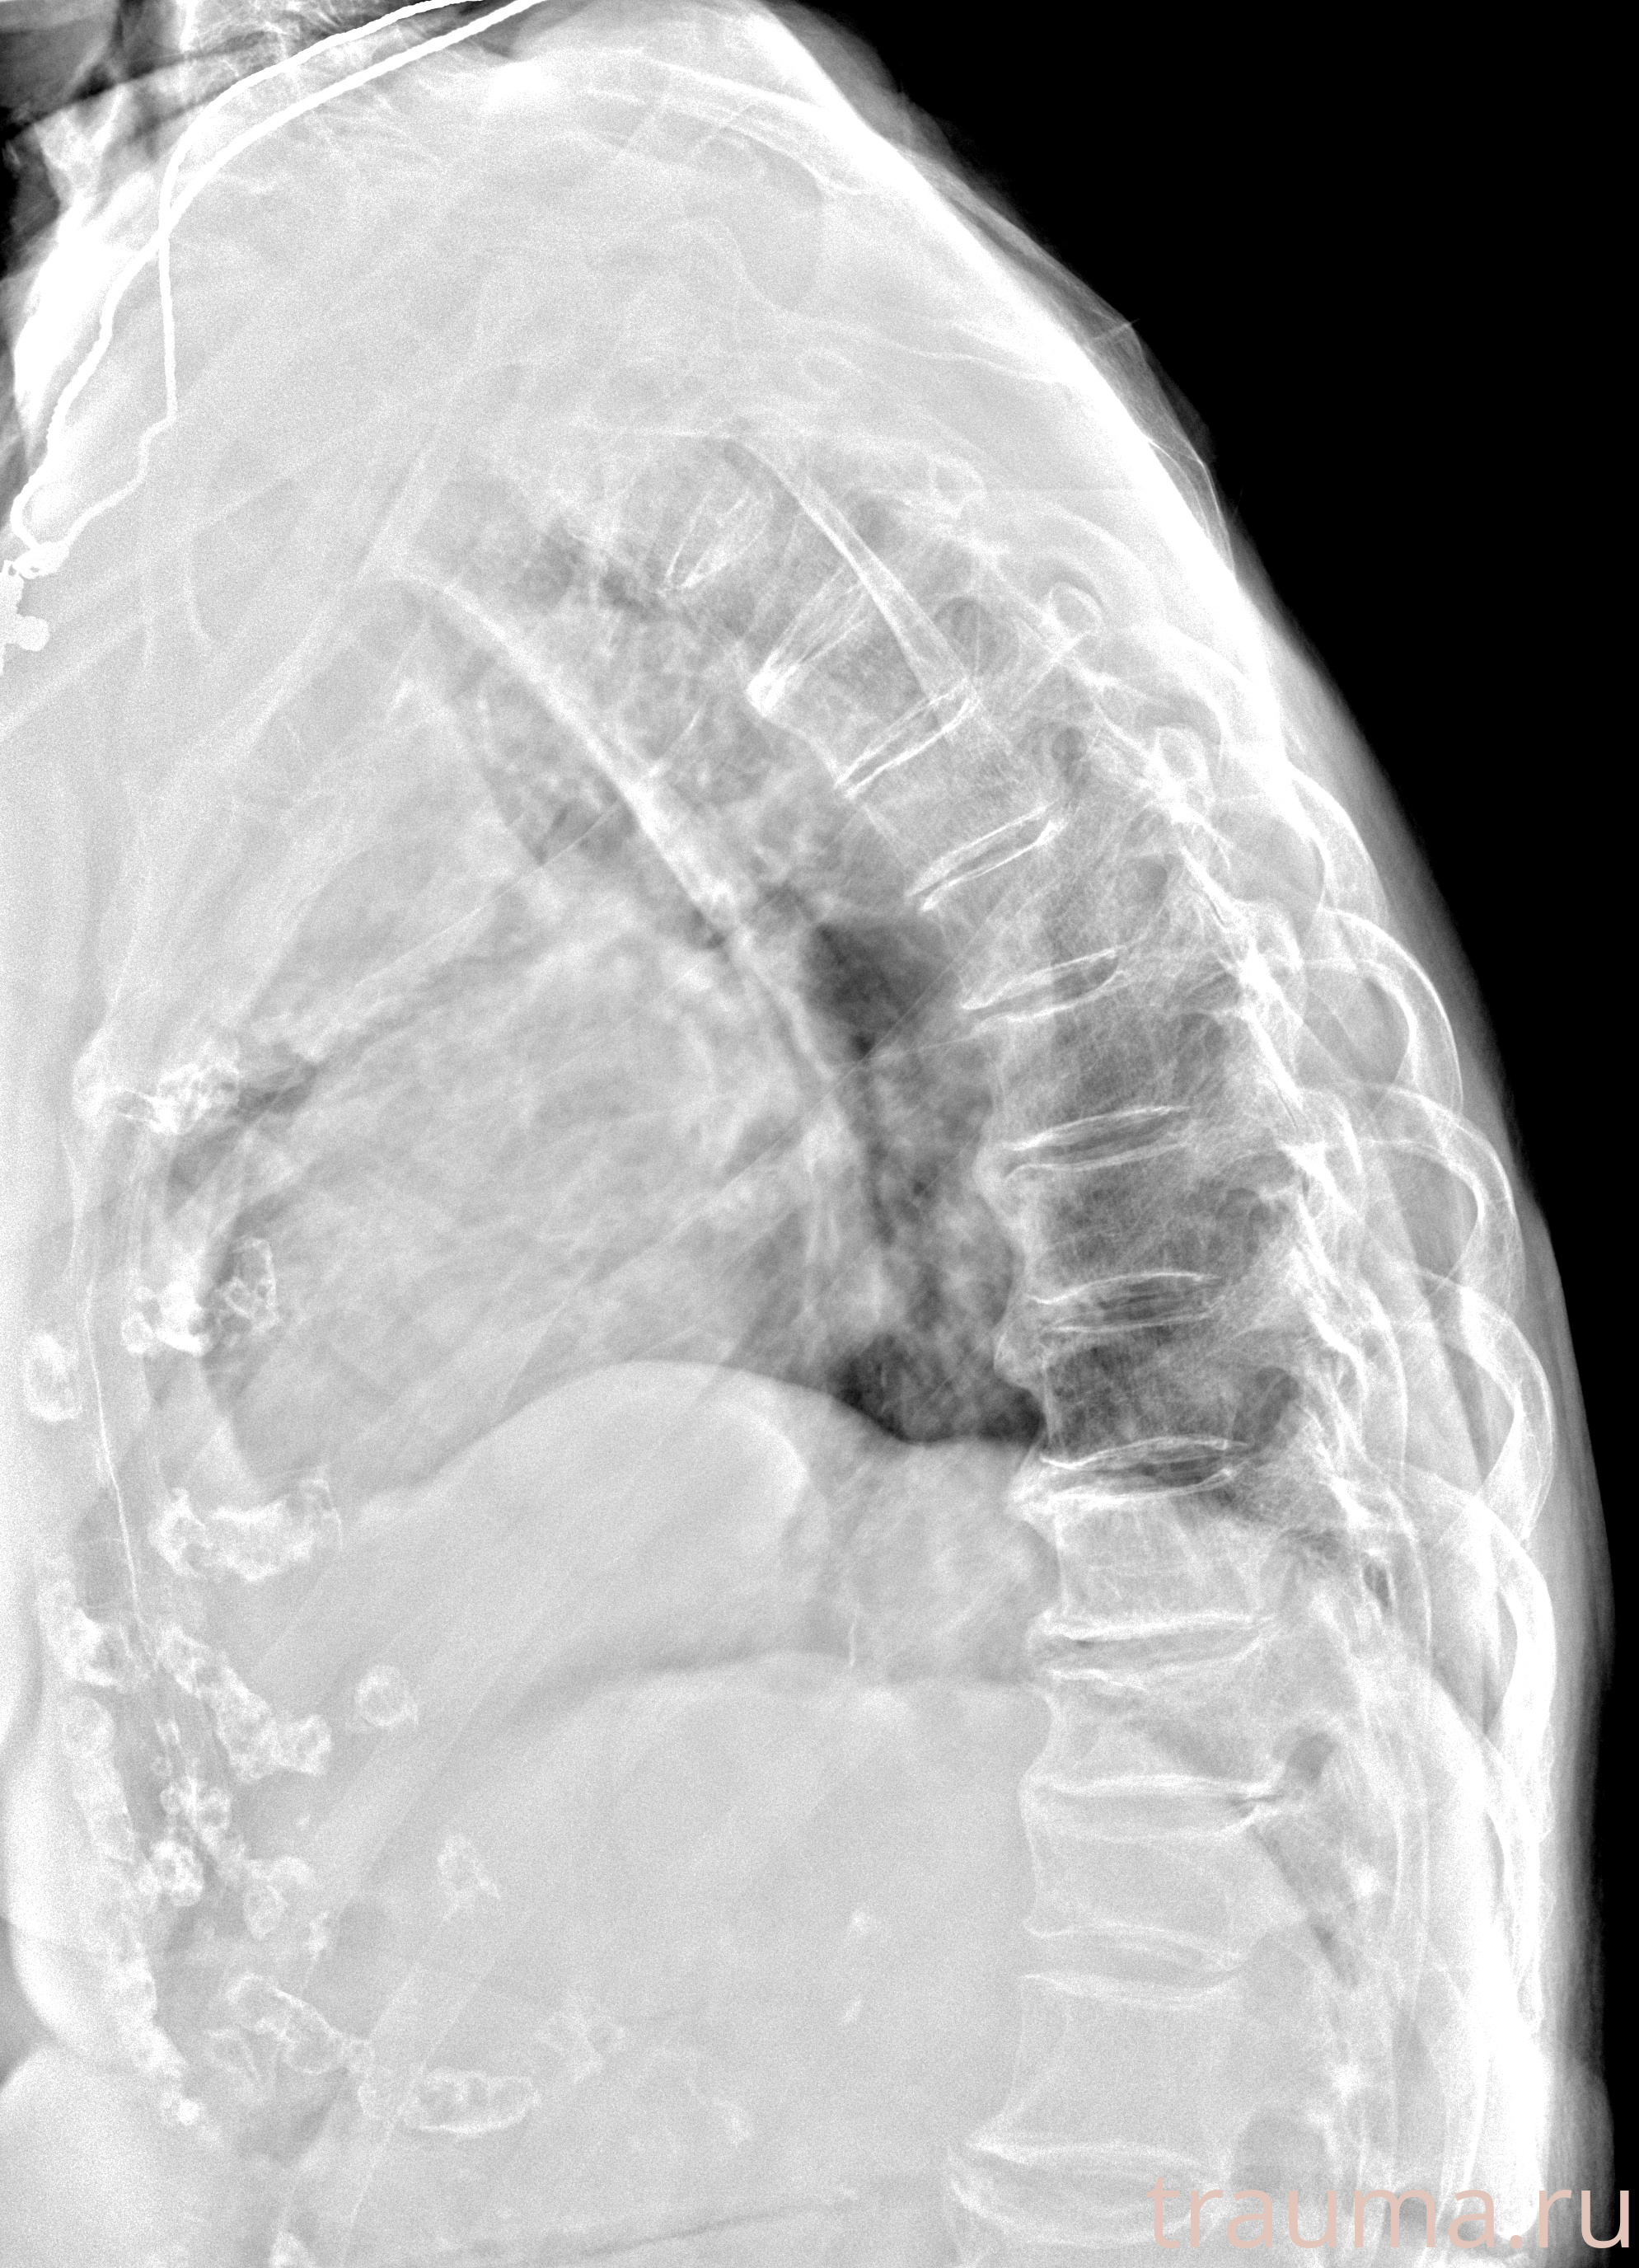

Рентген на дому: по вашему адресу приезжает врач-рентгенолог, травматолог-ортопед с мобильным рентгеновским аппаратом, проводит диагностику травмы или заболевания, делает необходимые рентгенограммы, дает рекомендации по дальнейшему лечению. Получить качественные снимки в домашних условиях возможно благодаря уникальной методике, разработанной МосРентген Центром для института  Склифосовского